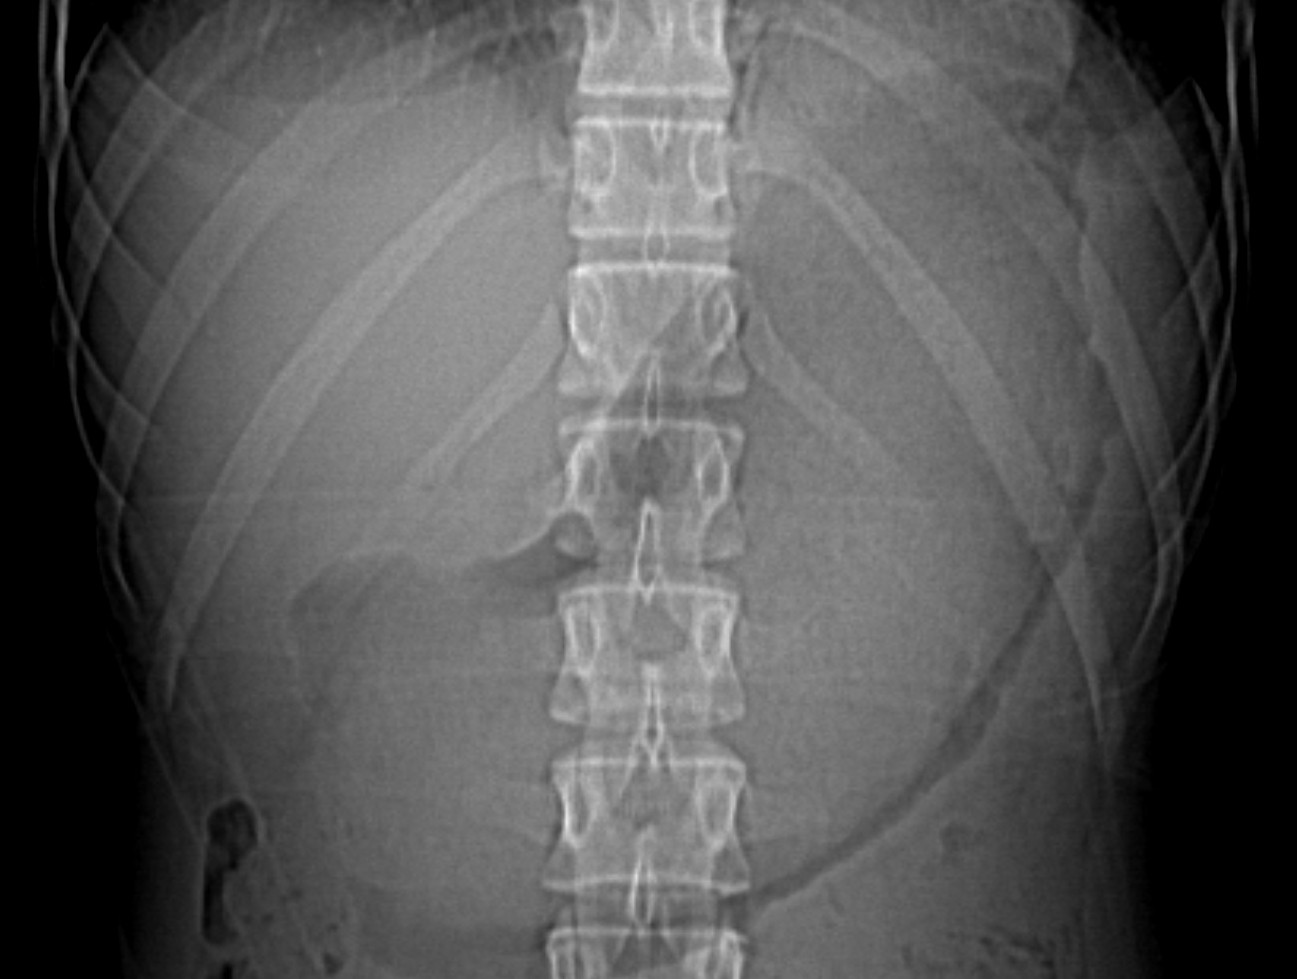

Se realiza radiografía simple de abdomen:

- Radiografía simple: manchas radiotransparentes en el intersticio de un masa sólida. Signos indirectos de obstrucción intestinal. Cuando el bezoar es pequeño, el difícil el diagnóstico a través de la placa simple, además de que pueden confundirse con abscesos o heces si se localizan en el colon.